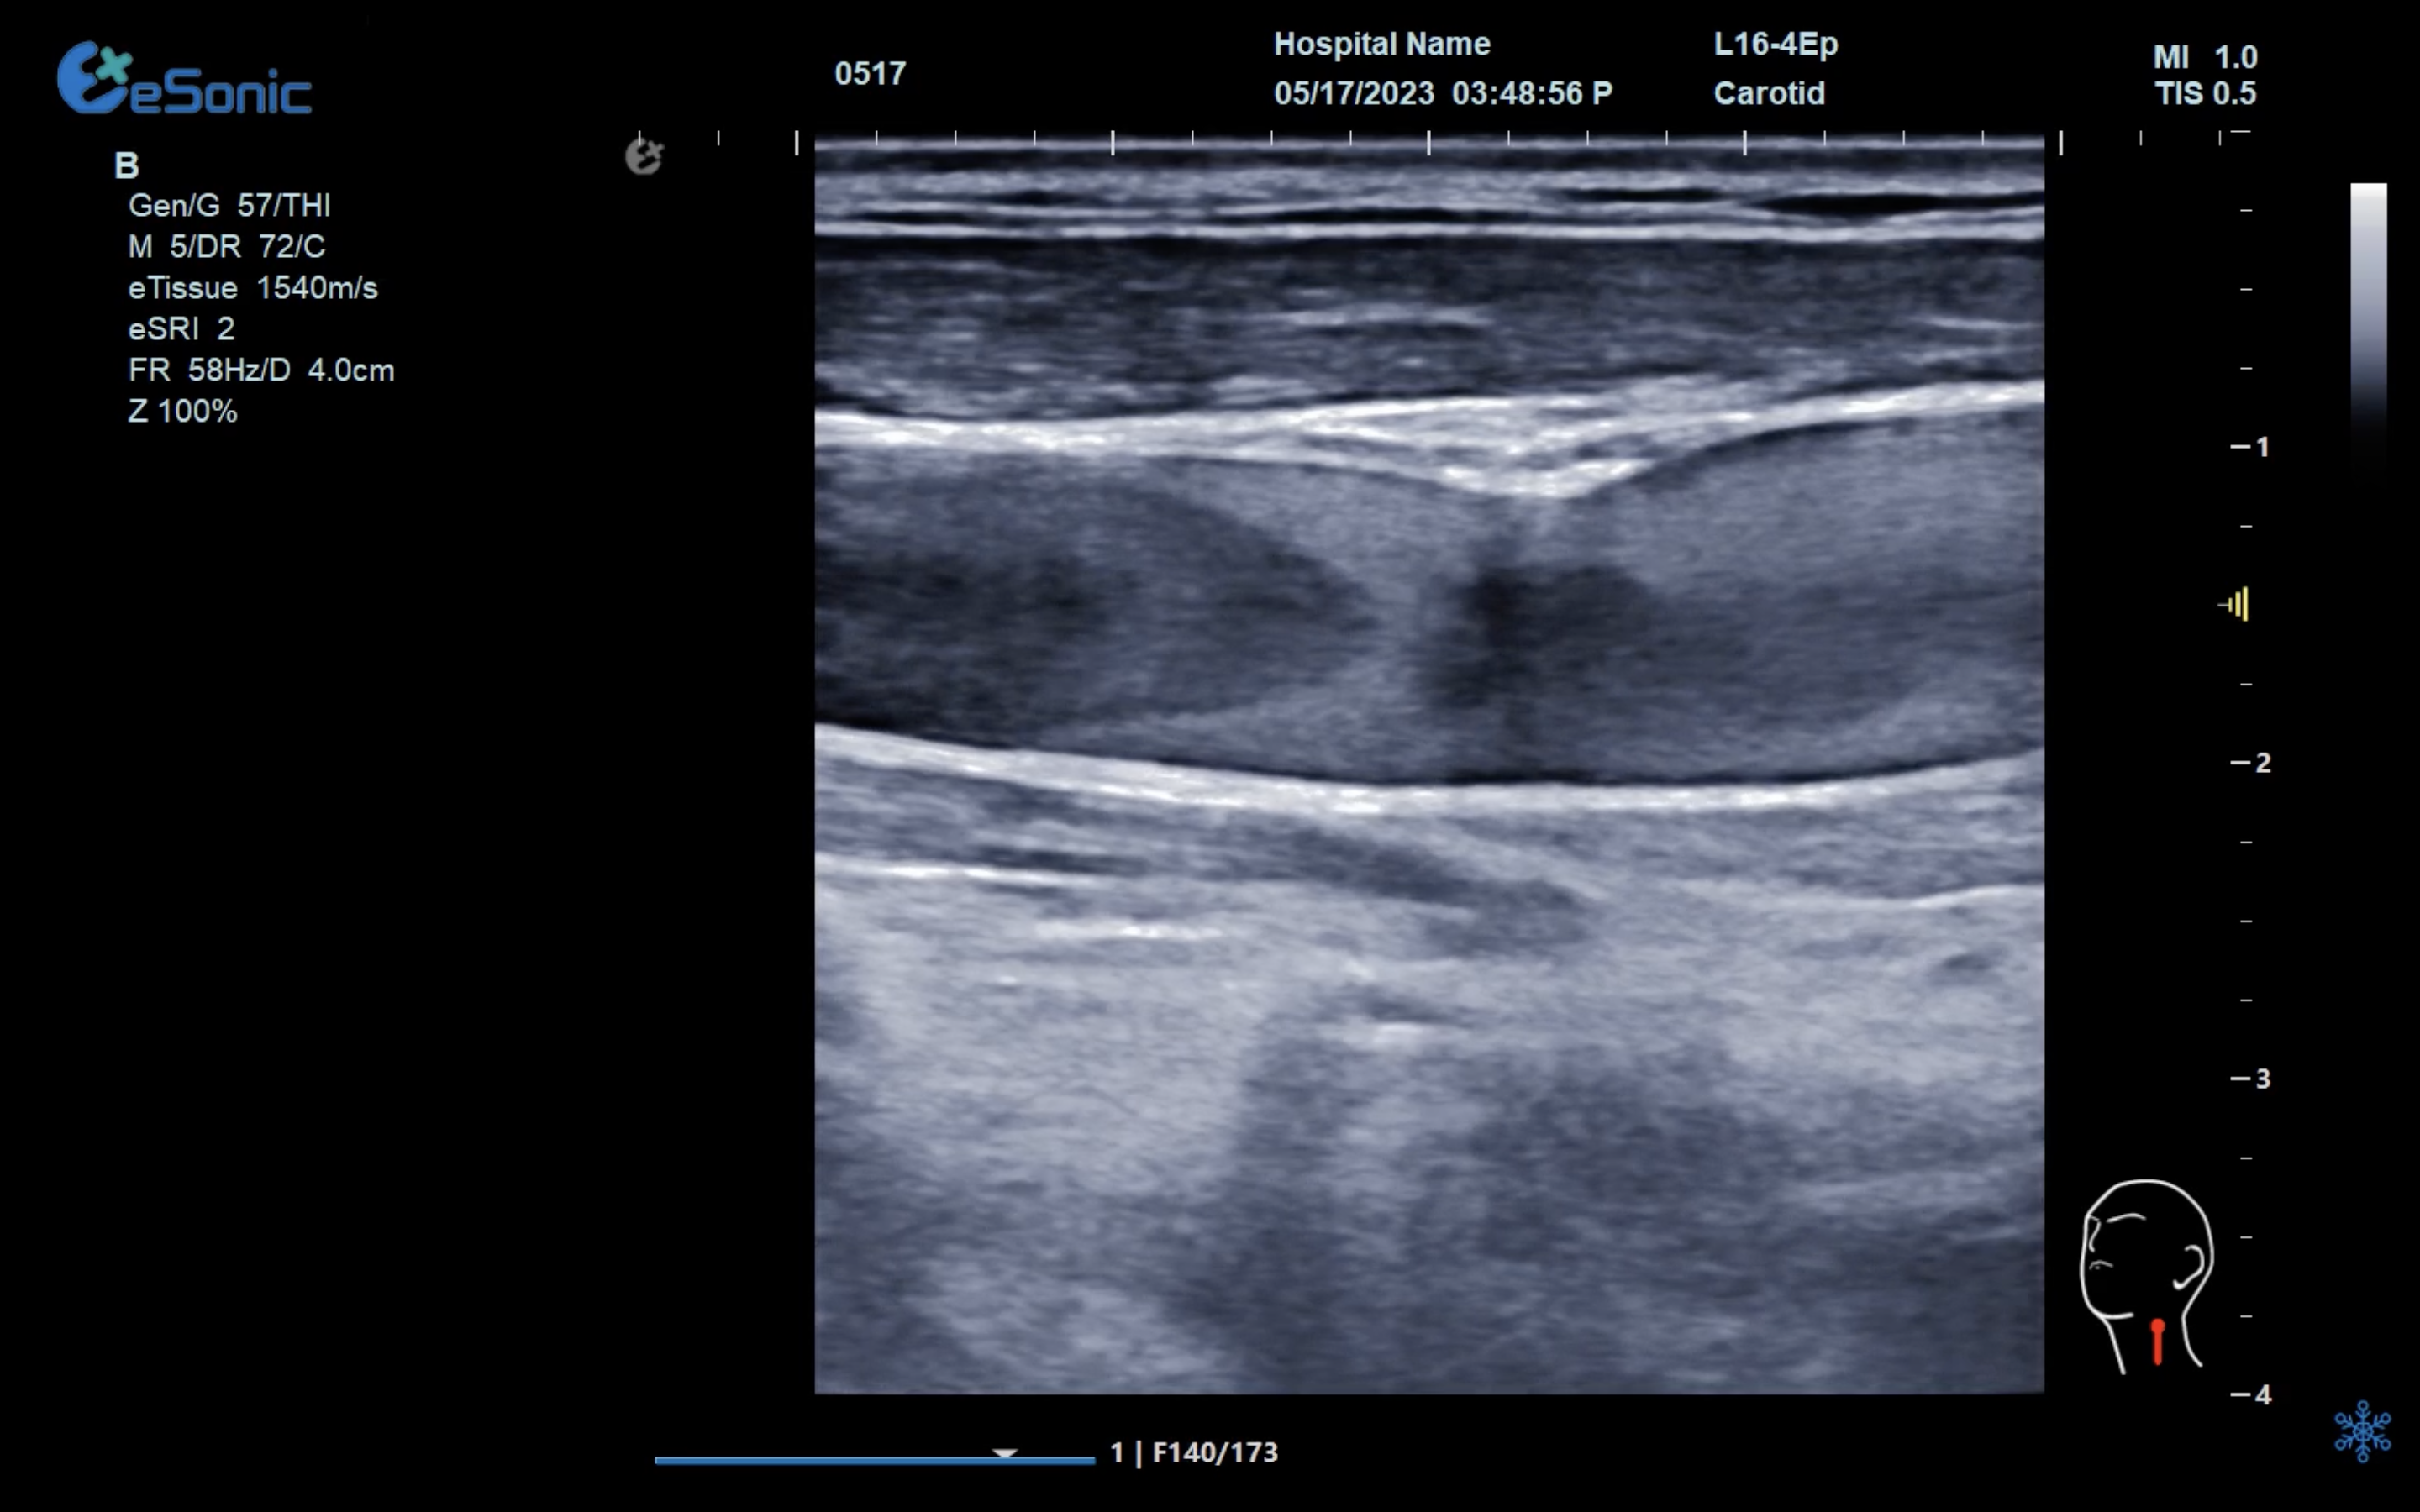

颈部血管